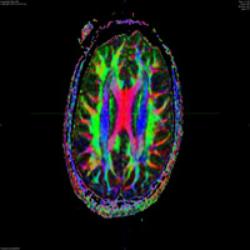

Purdue And GE Healthcare Advance Imaging Innovation In New Facility

A long and productive history of research between Purdue's Weldon School of Biomedical Engineering and GE Healthcare will serve as a framework for future innovation in a new medical imaging facility dedicated today at the Purdue Research Park. The facility includes a state-of-the-art 3-Tesla MRI system. The planned research builds on previous collaborative efforts between biomedical engineering and GE to perform key safety studies for fast scan MRI techniques and to enhance images from Computed Tomography (CT) systems.